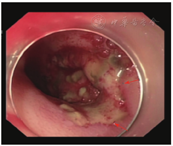

患者生命体征平稳,入院后未再次便血,暂予禁食水、补液、抑酸处理,给予200 mL氨甲环酸氯化钠注射液止血、2 U悬浮红细胞输注。2020年11月1日9:00复查血红蛋白为66 g/L,生命体征平稳,无便血,继续给予内科保守治疗并观察。11月2日4:22患者排大量(约500 mL)鲜血便,伴意识模糊,血压为57/35 mmHg,急查血常规示红细胞计数为0.85×109/L,血红蛋白为26 g/L,平均红细胞体积为93 fL,平均红细胞血红蛋白含量为30 pg,平均红细胞血红蛋白浓度为329 g/L。11月2日8:22急诊行第1次结肠镜检查,在直肠下段可见溃疡糜烂面,边界清楚,有黄苔附着,表面见大小约3.0 cm×2.5 cm的陈旧血块,未见明显活动性出血;进镜至回盲部观察3 min,未见血液从小肠流出;退镜过程中可见结肠腔内大量血凝块,反复冲洗未见新鲜出血(图2)。肠镜退出后20 min,患者再次排出大量(约500 mL)鲜血便,伴意识丧失。给予患者双通道加压补液、血管活性药物泵入、4 U悬浮红细胞输注、400 mL新鲜冰冻血浆输注后,收缩压上升至60~90 mmHg,意识稍有恢复。11月2日11:02急诊行全腹部+盆腔增强CT检查,动脉期、门脉期扫描示胰尾部与结肠间类圆形病灶明显强化,程度均与动脉相近,最大密度投影重建图像示病灶与脾动脉、结肠脾曲相连(图3A);延迟期扫描示结肠脾曲左侧肠腔内可见密度增高,提示肠腔内对比剂进入(图3B)。考虑脾动脉瘤破裂致结肠脾曲活动性出血。11月2日13:35行第2次结肠镜检查,进镜至结肠脾曲,可见黏膜隆起伴充血肿胀,顶端可见糜烂,有白色血栓头附着,未见活动性出血,以肠镜触碰血栓头可见鲜红色血液喷出(图4A);予以钛夹夹闭出血动脉,夹闭过程中可见大量活动性出血,6枚钛夹夹闭后暂无活动性出血(图4B)。结肠镜下止血后,患者仍持续排出少量血便(约80 mL/h),收缩压为80~100 mmHg。考虑动脉瘤破裂致结肠脾曲出血,钛夹止血不彻底,病因不能去除,仍有出血可能,遂于11月2日15:05行数字减影血管造影(digital subtraction angiography,DSA),可见脾动脉瘤样扩张,最大径为4.2 cm(图5A),证实为脾动脉真性动脉瘤,但未发现对比剂大量外渗,考虑因患者血压较低暂未出血或内镜下钛夹成功止血;在瘤体左侧可见结肠腔内的钛夹,证明存在脾动脉瘤结肠脾曲瘘。采用介入导管超选至脾动脉,置入6枚弹簧圈栓塞,再次造影未见对比剂溢出,动脉瘤不再显影(图5B)。11月3日患者排出少量血便,但生命体征平稳。术后1周复查增强CT示脾动脉栓塞术后,脾动脉瘤腔内未见对比剂进入,肠腔未见活动性出血。术后2周患者无便血、腹痛等不适,恢复进食后粪便常规和隐血试验均阴性,复查血红蛋白为97 g/L,康复出院。随访1.5年,患者未再便血,血红蛋白、血小板计数均在正常参考值范围内,粪便常规检查未见异常。